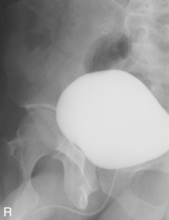

AP and posterior oblique critique

• Supine, midsagittal plane aligned and centered to centerline, support placed under knees, no rotation

• Erect, midsagittal plane aligned and centered to centerline, no rotation

• Center IR to iliac crest—ensure that bladder area, including the symphysis pubis, is included at lower IR margin.

(RPO, LPO, and Optional Lateral)

Note: Cystogram routine may not include a lateral because of high gonadal dose.